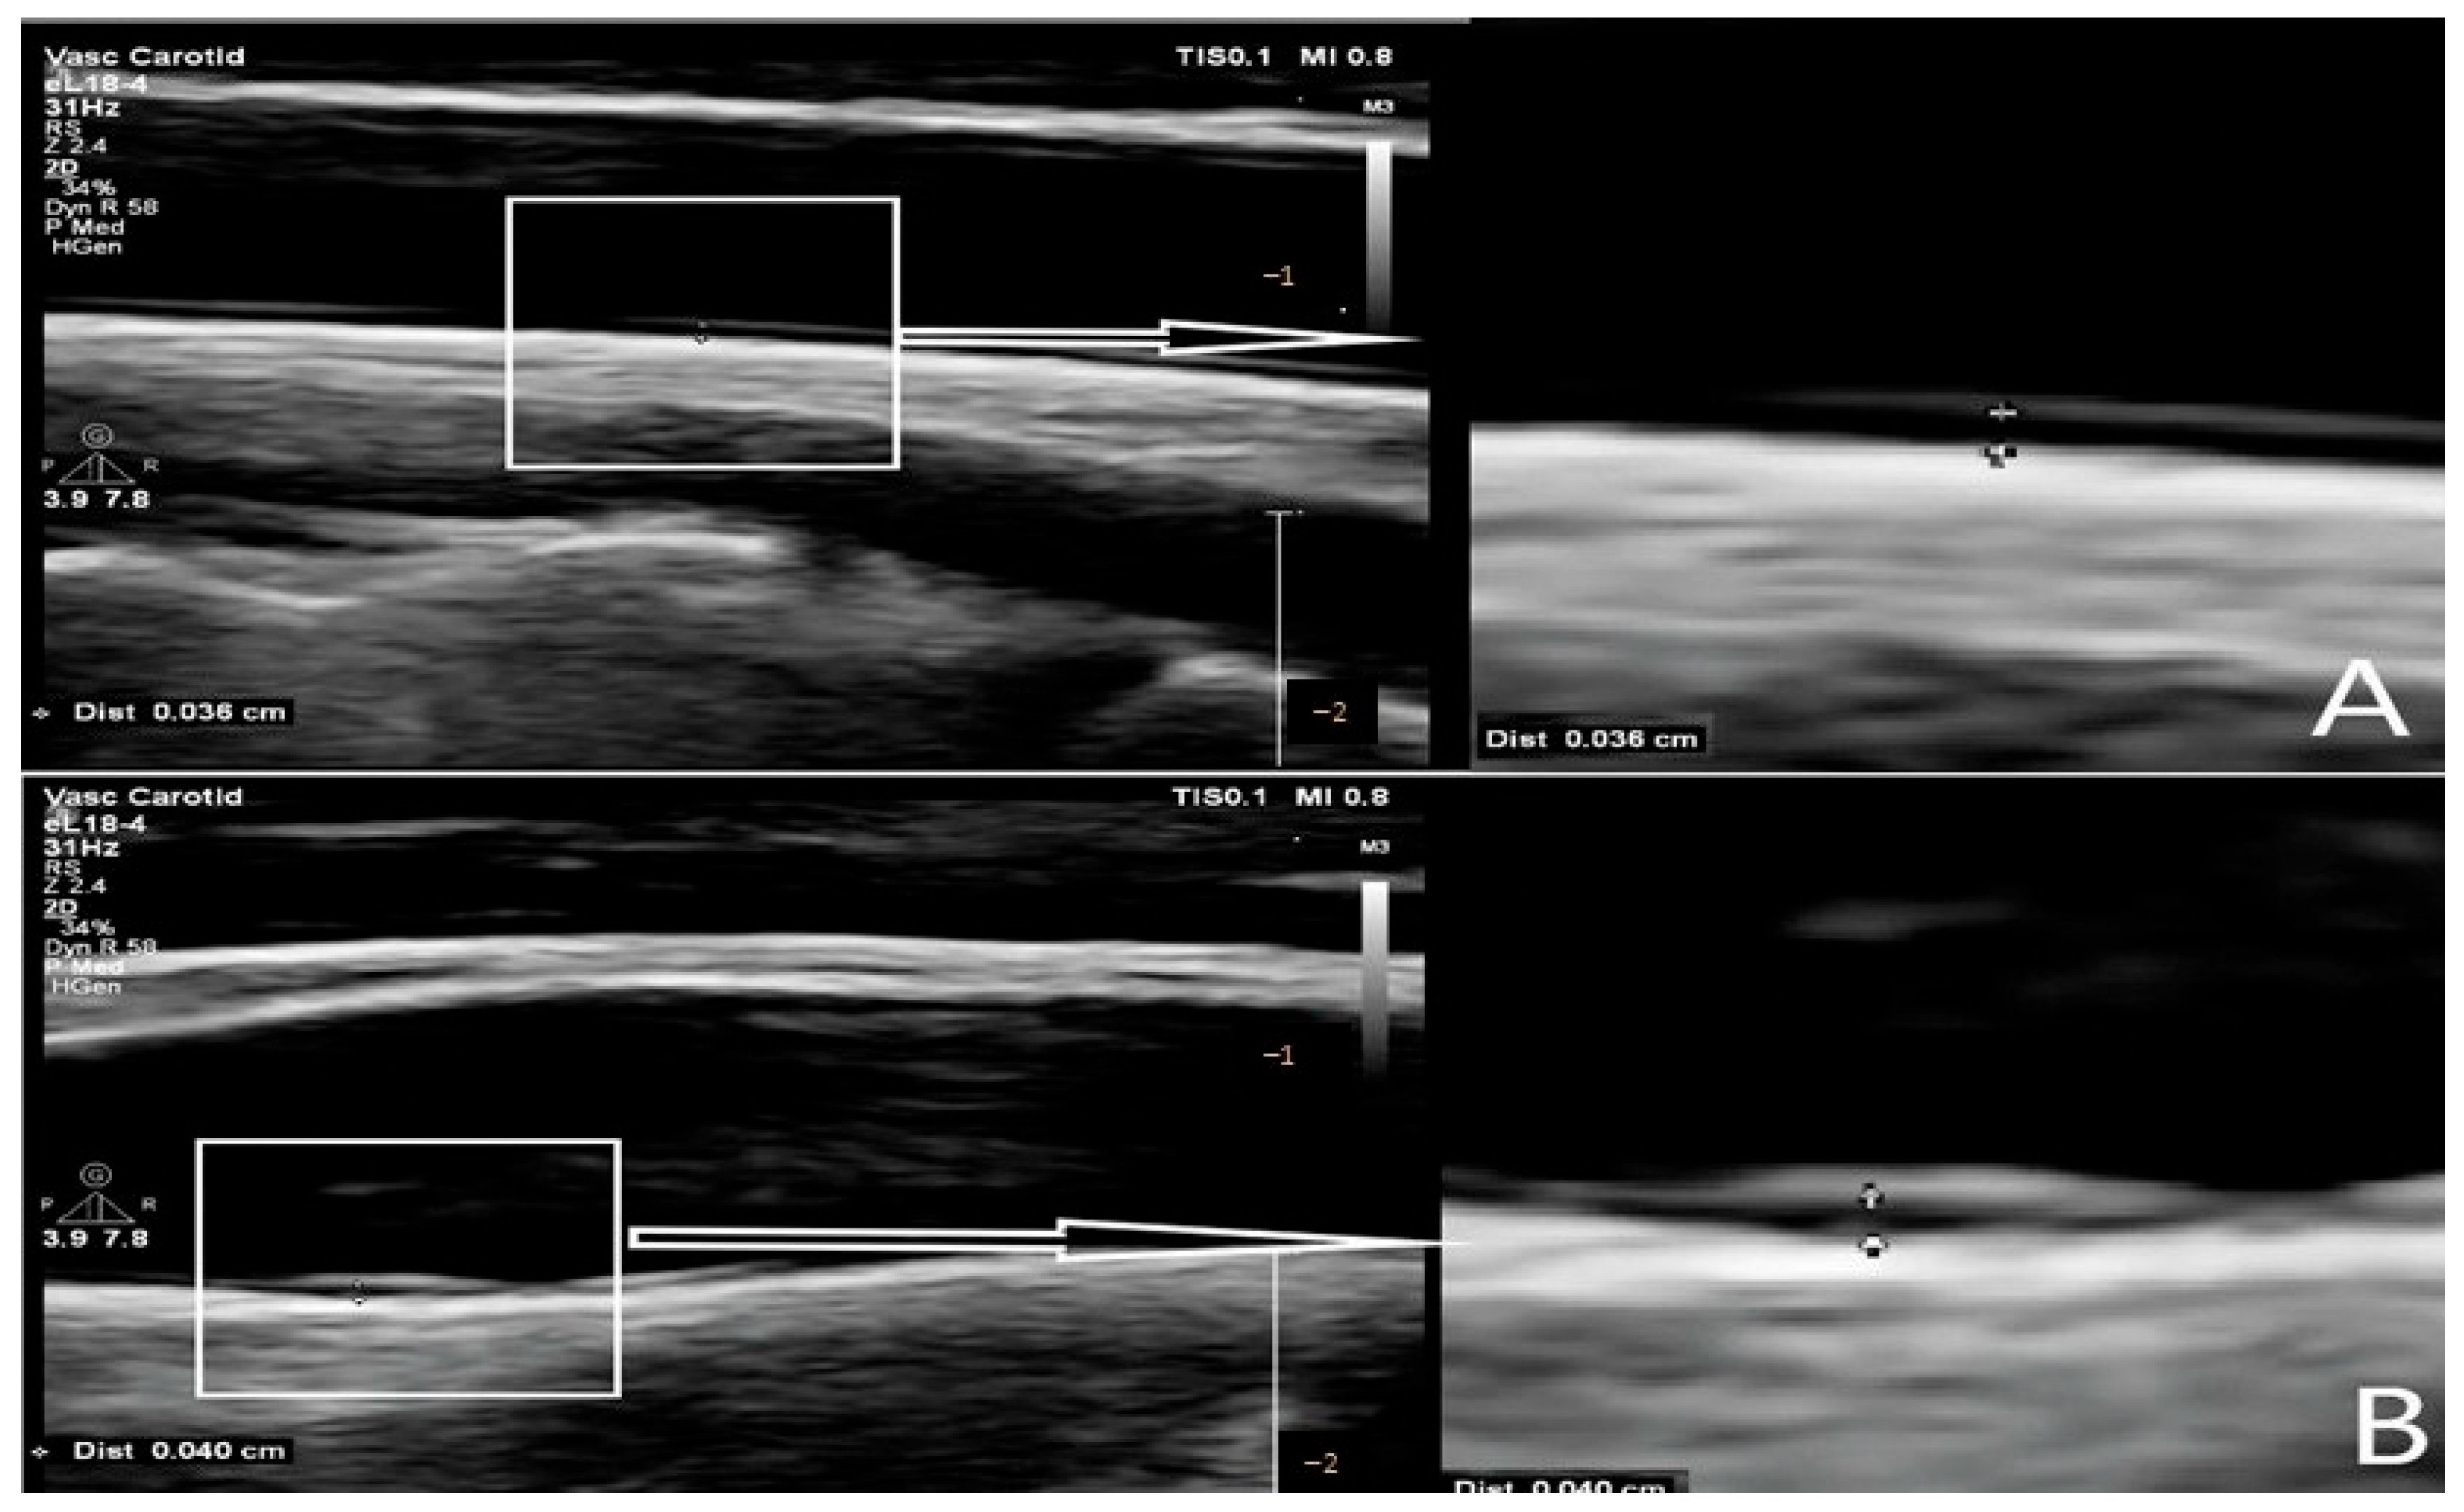

2.1. Carotid Intima–Media Thickness (CIMT)

| CAROTID INTIMA–MEDIA THICKNESS | |||

| ❖ Right side | |||

| The bulb | 0.43 (0.36–0.59) | 0.33 (0.29–0.39) | <0.001 |

| The middle segment of the CCA | 0.37 (0.32–0.46) | 0.31 (0.26–0.36) | |

| ❖ Left side | |||

| The bulb | 0.43 (0.36–0.60) | 0.35 (0.29–0.39) | <0.001 |

| The middle segment of the CCA | 0.37 (0.33–0.47) | 0.32 (0.27–0.37) | |